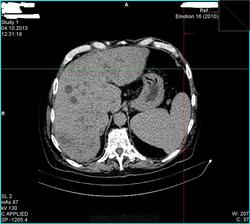

- https://radiomed.ru/sites/default/files/styles/case_slider_image/public/user/15361/00bd452f.jpg?itok=7Yqpn566

- https://radiomed.ru/sites/default/files/styles/case_slider_image/public/user/15361/00bfee95.jpg?itok=PUcrVzyc

- https://radiomed.ru/sites/default/files/styles/case_slider_image/public/user/15361/00c0937f.jpg?itok=7U4D1tv_

- https://radiomed.ru/sites/default/files/styles/case_slider_image/public/user/15361/00ca7eed.jpg?itok=rr_xi6tP

- https://radiomed.ru/sites/default/files/styles/case_slider_image/public/user/15361/00cb6df1.jpg?itok=1nPv330F

- https://radiomed.ru/sites/default/files/styles/case_slider_image/public/user/15361/00cb352d.jpg?itok=EVSnuZCO

- https://radiomed.ru/sites/default/files/styles/case_slider_image/public/user/15361/00cce936.jpg?itok=PqpE7v3O

- https://radiomed.ru/sites/default/files/styles/case_slider_image/public/user/15361/00cd0fba.jpg?itok=XHp74aU2

- https://radiomed.ru/sites/default/files/styles/case_slider_image/public/user/15361/00cd29f9.jpg?itok=H17OxJCX

Контраст тоже не завезли? Блок БДС возможен.

Тоже вижу расширенные желчные протоки. Освойте экспорт изображений в формате дайком, тогда сможете размещать из на сайте, советы будут более предметными.

+1. Дайте дайкомы посмотреть. Возможна обструкция интрапанкреатической части холедоха или еще ниже. А для итерпретации очагов в печени желательно контрастное усиление сделать.

При патологии печени очень желательно указывать наличие/отсутствие болевого синдрома, желтухи. Большинство КТ-исследований гепато-панкреато-дуоденальной зоны (а эта зона является одной из самых трудно трактуемых в брюшной полости) без контраста является мало информативным способом облучения пациента . Фокусные изменения и расширение внутрипеченочных желчных протоков было видно и на УЗИ. Понятно, что не всегда есть контраст, но ... в-общем, попробуем выжать максимум из имеющегося, если у Вас получится закинуть архив дайкома на файлообменник.

. Фокусные изменения и расширение внутрипеченочных желчных протоков было видно и на УЗИ. Понятно, что не всегда есть контраст, но ... в-общем, попробуем выжать максимум из имеющегося, если у Вас получится закинуть архив дайкома на файлообменник.